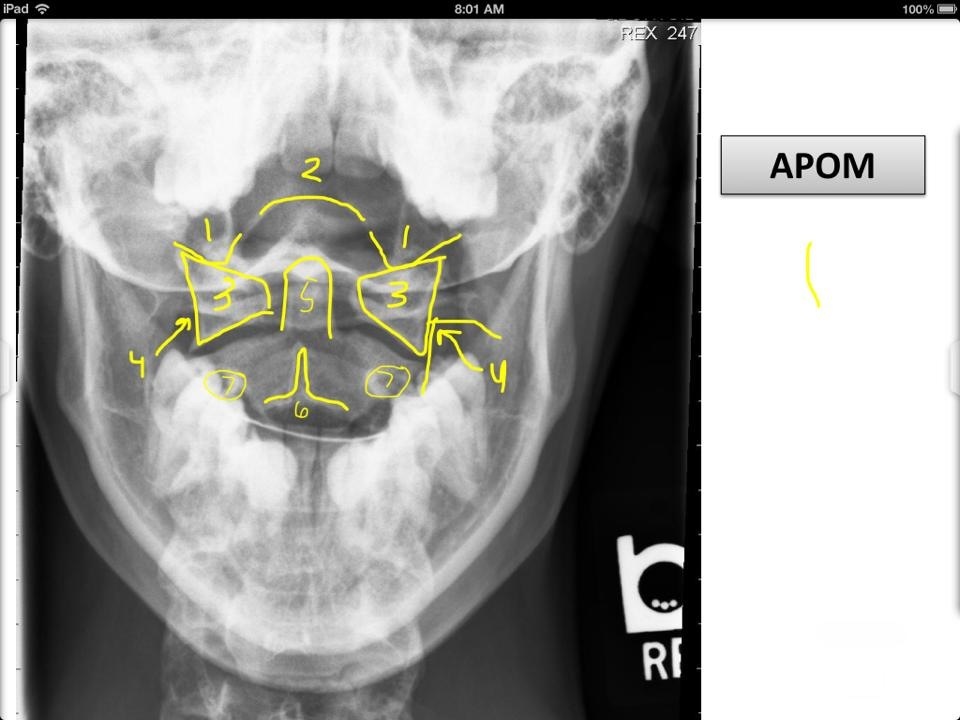

7

1

Ocipital Condyles

8

2

Foramen Magnum

9

3

Lateral Masses of C1

10

4

C1 TVP/Lateral Mass Junction

11

5

Odontoid Process

12

6

C2 Spinous Process

13

C2 Pedicle shadow